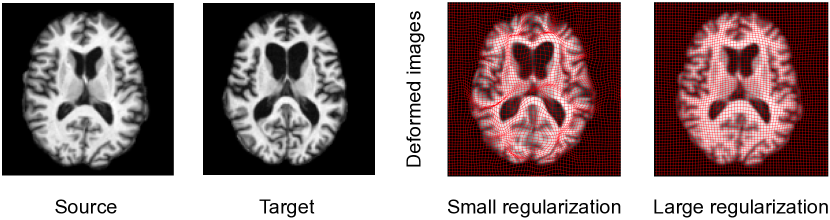

To ensure the smoothness of transformation fields, a regularization term defined on the tangent space of diffeomorphisms (called velocity fields) is often introduced in registration models. Having such a regularity with proper model parameters is critical to registration performance because they greatly affect the estimated transformations. Either too large or small-valued regularity can not achieve satisfying registration results (as shown in Fig .1). Models of handling the regularity parameter mainly include (i) direct optimizing a Bayesian model or treating it as a latent variable to integrate out via Expectation Maximization (EM) algorithm (Allassonnière et al., 2007; Allassonnière and Kuhn, 2008; Zhang et al., 2013; Wang and Zhang, 2021), (ii) exhaustive search in the parameter space (Jaillet et al., 2005; Valsecchi et al., 2013; Ruppert et al., 2017), and (iii) utilizing parameter continuation methods (Haber et al., 2000; Haber and Modersitzki, 2006; Mang and Biros, 2015; Mang et al., 2019). Direct optimization approaches define a posterior of transformation fields that includes an image matching term as a likelihood and a regularization as a prior to support the smoothness of transformations (Zöllei et al., 2007; Allassonnière and Kuhn, 2008; Toews and Wells, 2009). Estimating regularization parameters of these models using direct optimization is not straightforward due to the complex structure of the posterior distribution. Simpson et al. infer the level of regularization in small deformation registration model by mean-field VB inference (Jordan et al., 1999), which allows tractable approximation of full Bayesian inference in a hierarchical probabilistic model (Simpson et al., 2012, 2015). However, these aforementioned algorithms are heavily dependent on initializations, and are prone to getting stuck in the local minima of high-dimensional and non-linear functions in the transformation space. A stochastic approximative expectation maximization (SAEM) algorithm (Allassonnière and Kuhn, 2008) was developed to marginalize over the posterior distribution of unknown parameters using a Markov Chain Monte Carlo (MCMC) sampling method. Later, Zhang et al. estimate the model parameters of regularization via a Monte Carlo Expectation Maximization (MCEM) algorithm for unbiased atlas building problem (Zhang et al., 2013). A recent model of Hierarchical Bayesian registration (Wang and Zhang, 2021) further characterizes the regularization parameters as latent variables generated from Gamma distribution, and integrates them out by an MCEM method.

Refer to caption

Figure 1: Left to right: examples of transformation fields overlaid with deformed images with under-regularized and over-regularized registration models. A small regularization introduces crossing artifacts on the transformations vs. a large regularization discourages sufficient transformations between images.